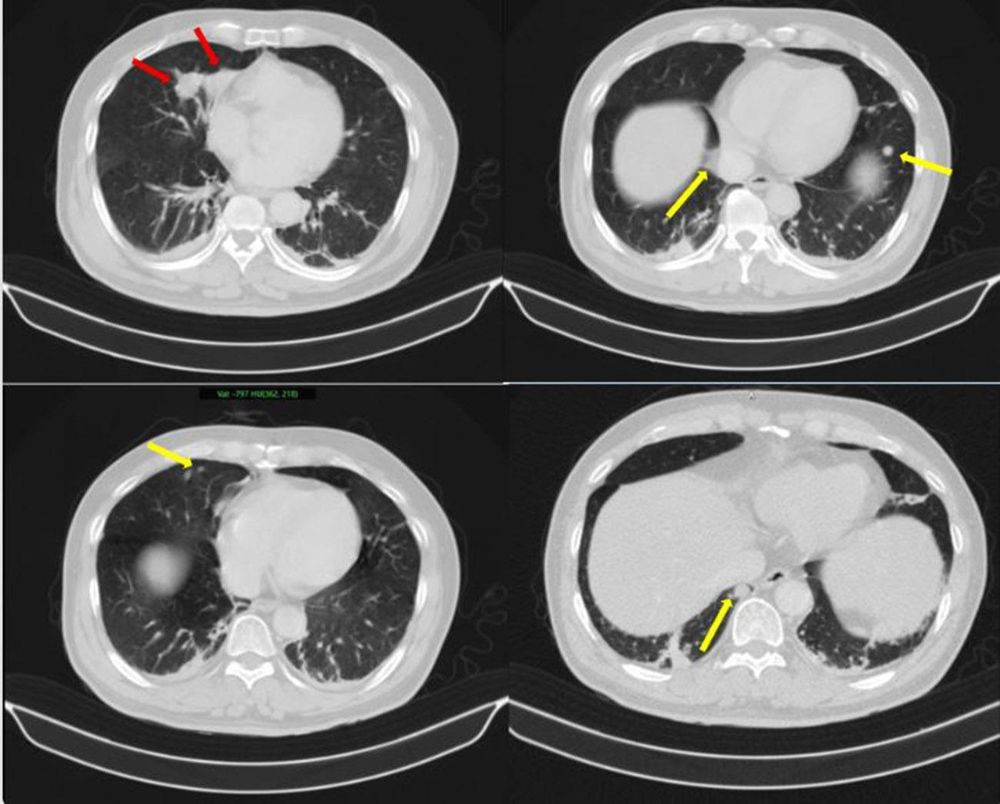

Những hình ảnh bất thường trên phổi của bệnh nhân (Ảnh: BV Bạch Mai)

Kết quả sinh thiết và phân tích mô bệnh học, kết hợp hóa mô miễn dịch, đã làm rõ bản chất bệnh lý: khối u tại phổi là ung thư biểu mô tuyến của phổi; trong khi đó, khối u tại tuyến tiền liệt là ung thư biểu mô tuyến với điểm Gleason 9 – thuộc nhóm nguy cơ cao. Đáng chú ý, hai loại ung thư này có nguồn gốc độc lập, không phải là hiện tượng di căn chéo.